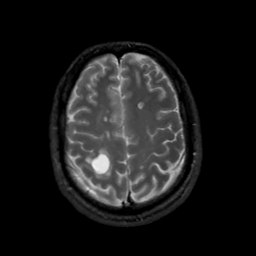

MR Study #7, March 24, 1991 -- Slice #38